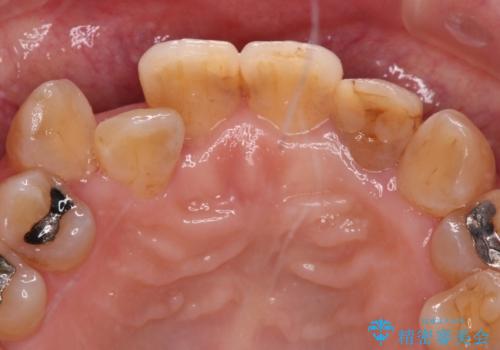

- 20年以上前に神経を取り除いた前歯の変色が気になるとのことで来院された患者様です。

レントゲン写真より、歯根の炎症が認められなかったため、ファイバーコアによる土台築製後、オールセラミッククラウンにて補綴することとしました。

また、真ん中の前歯はコンポジットレジンによる修復跡が目立っており、合わせてオールセラミッククラウンにて治療することとしました。